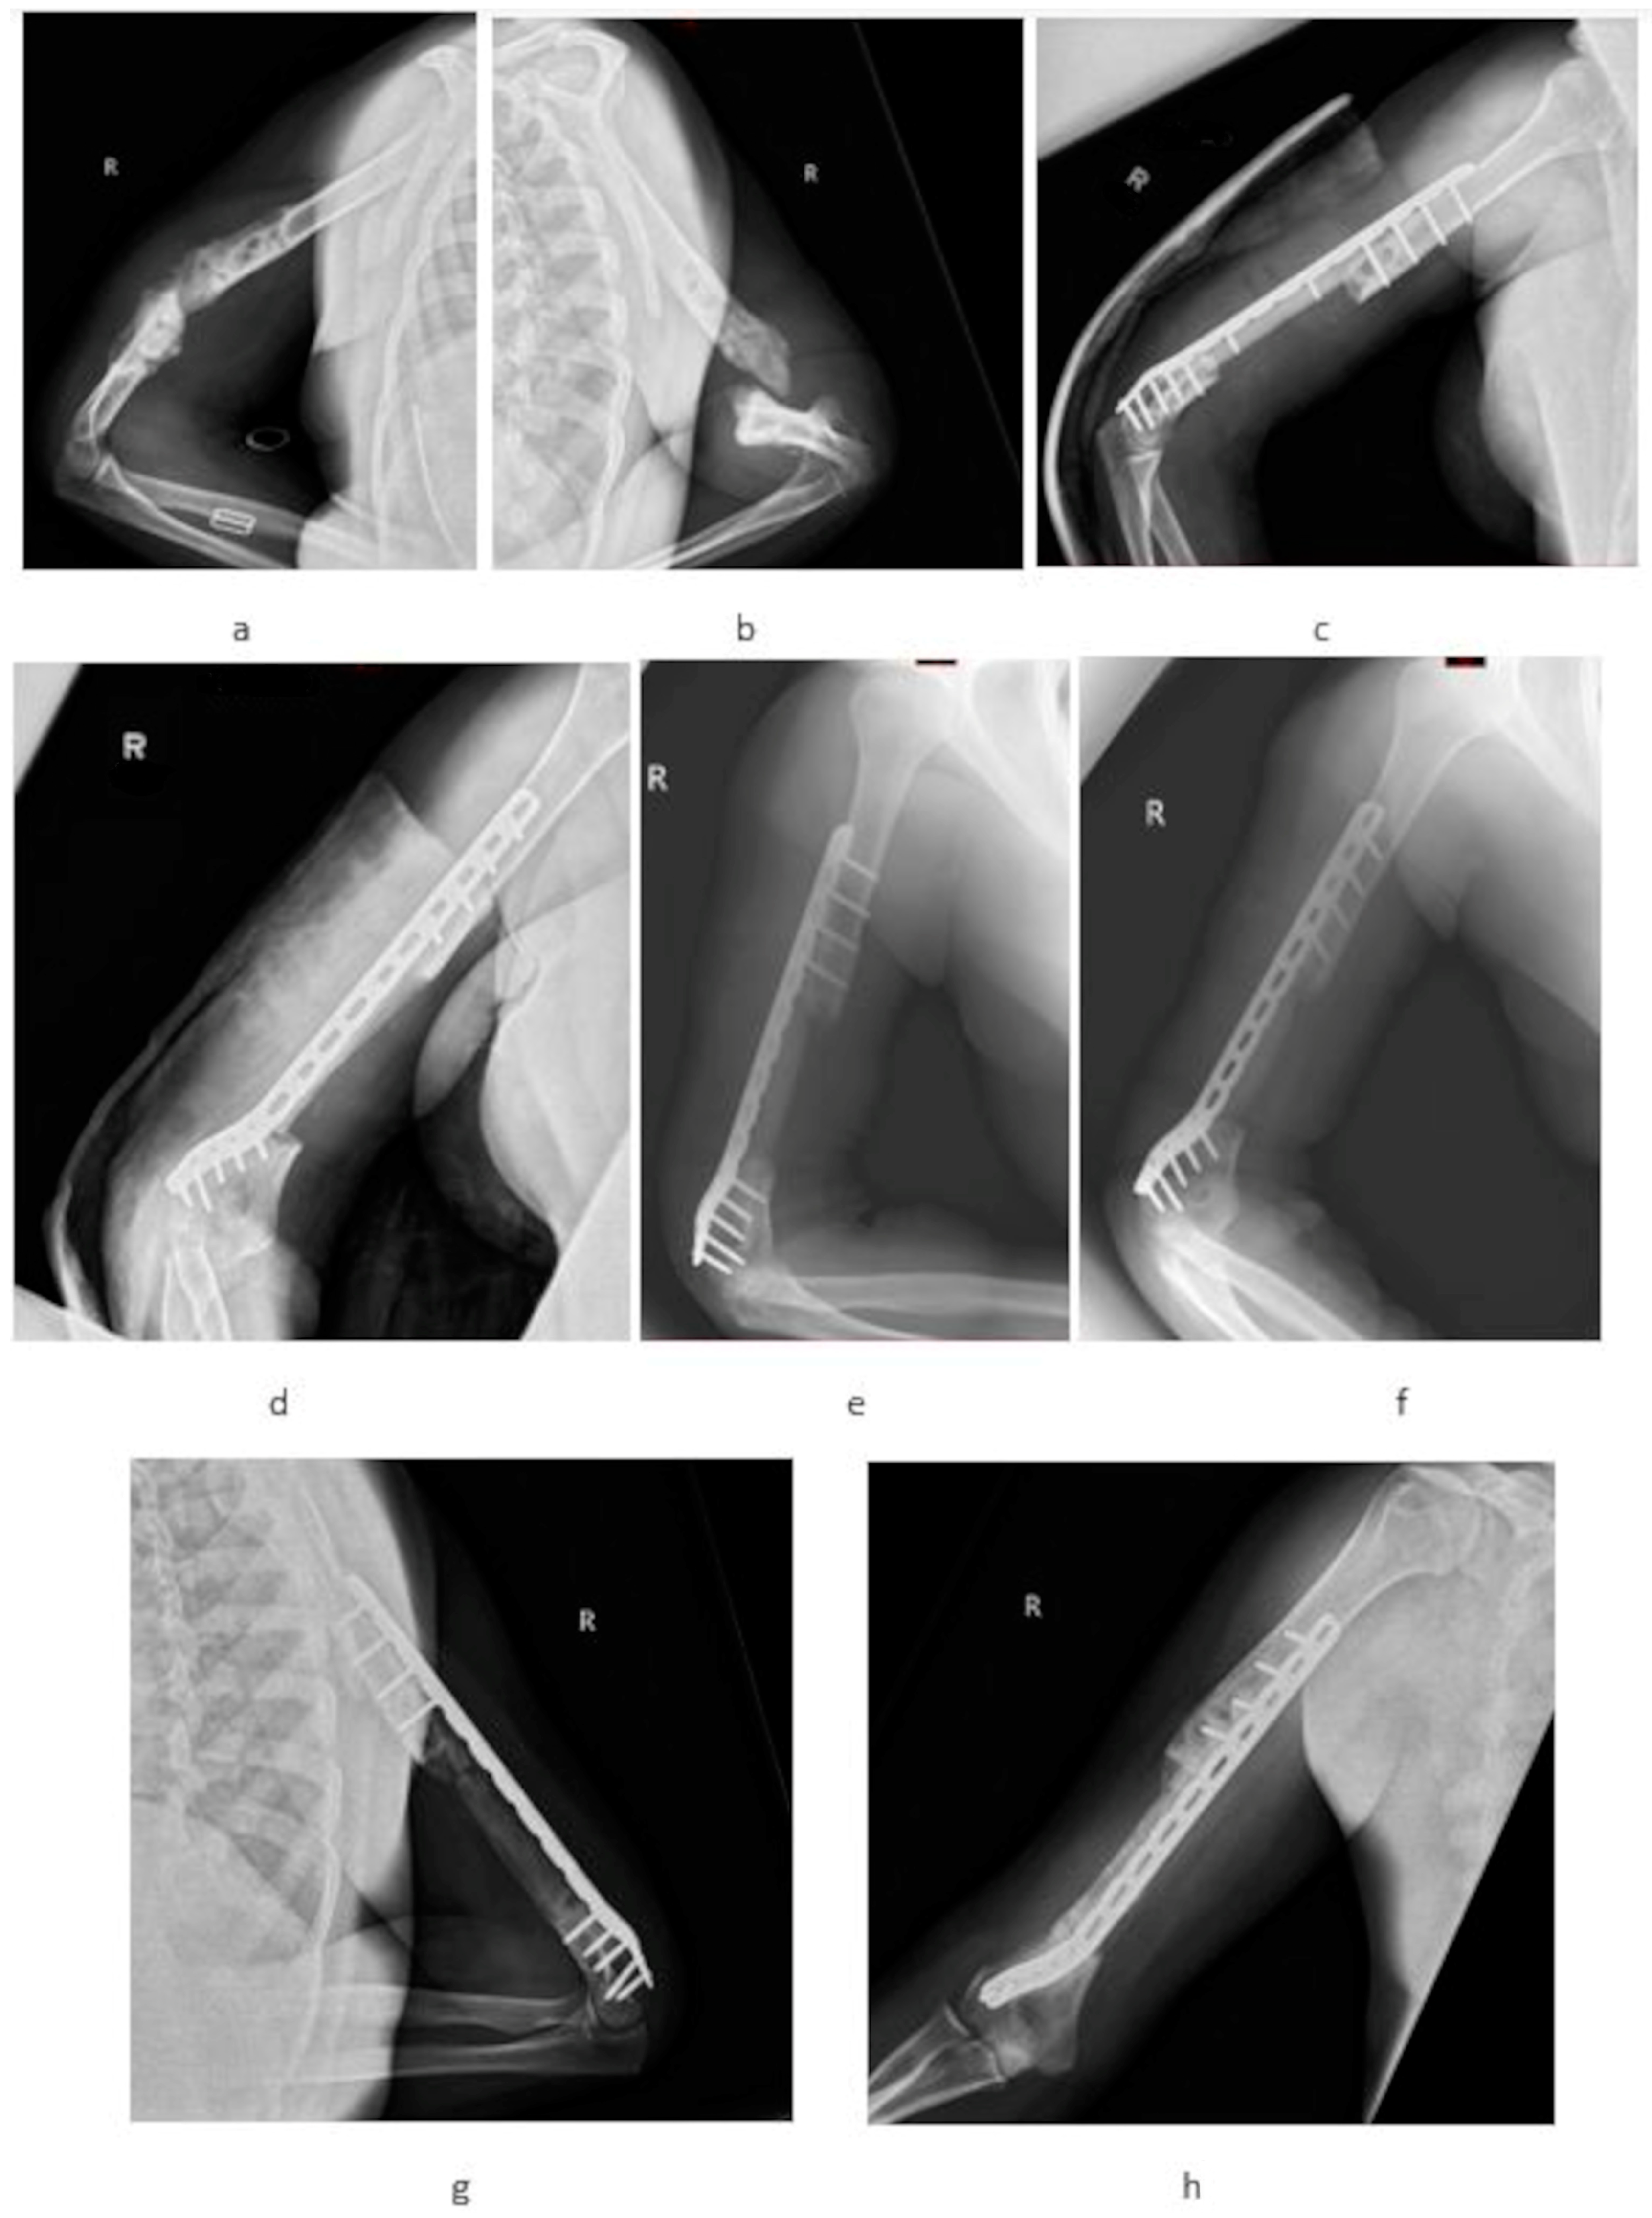

Clinical Observations of the Effectiveness of the Masquelet Induced Membrane Technique in the Treatment of Critical Long-Bone Defects of the Lower and Upper Extremities

| Localization | Arm: 7 | Femur: 11 | ---- |

| Radius: 8 | Tibia: 13 | ---- | |

| Ulna: 5 | Fibula: 1 | ---- | |

| Bone fixation | LCP: 20 (100%) | LCP: 12 (48%) IMN: 13 (52%) | --- |